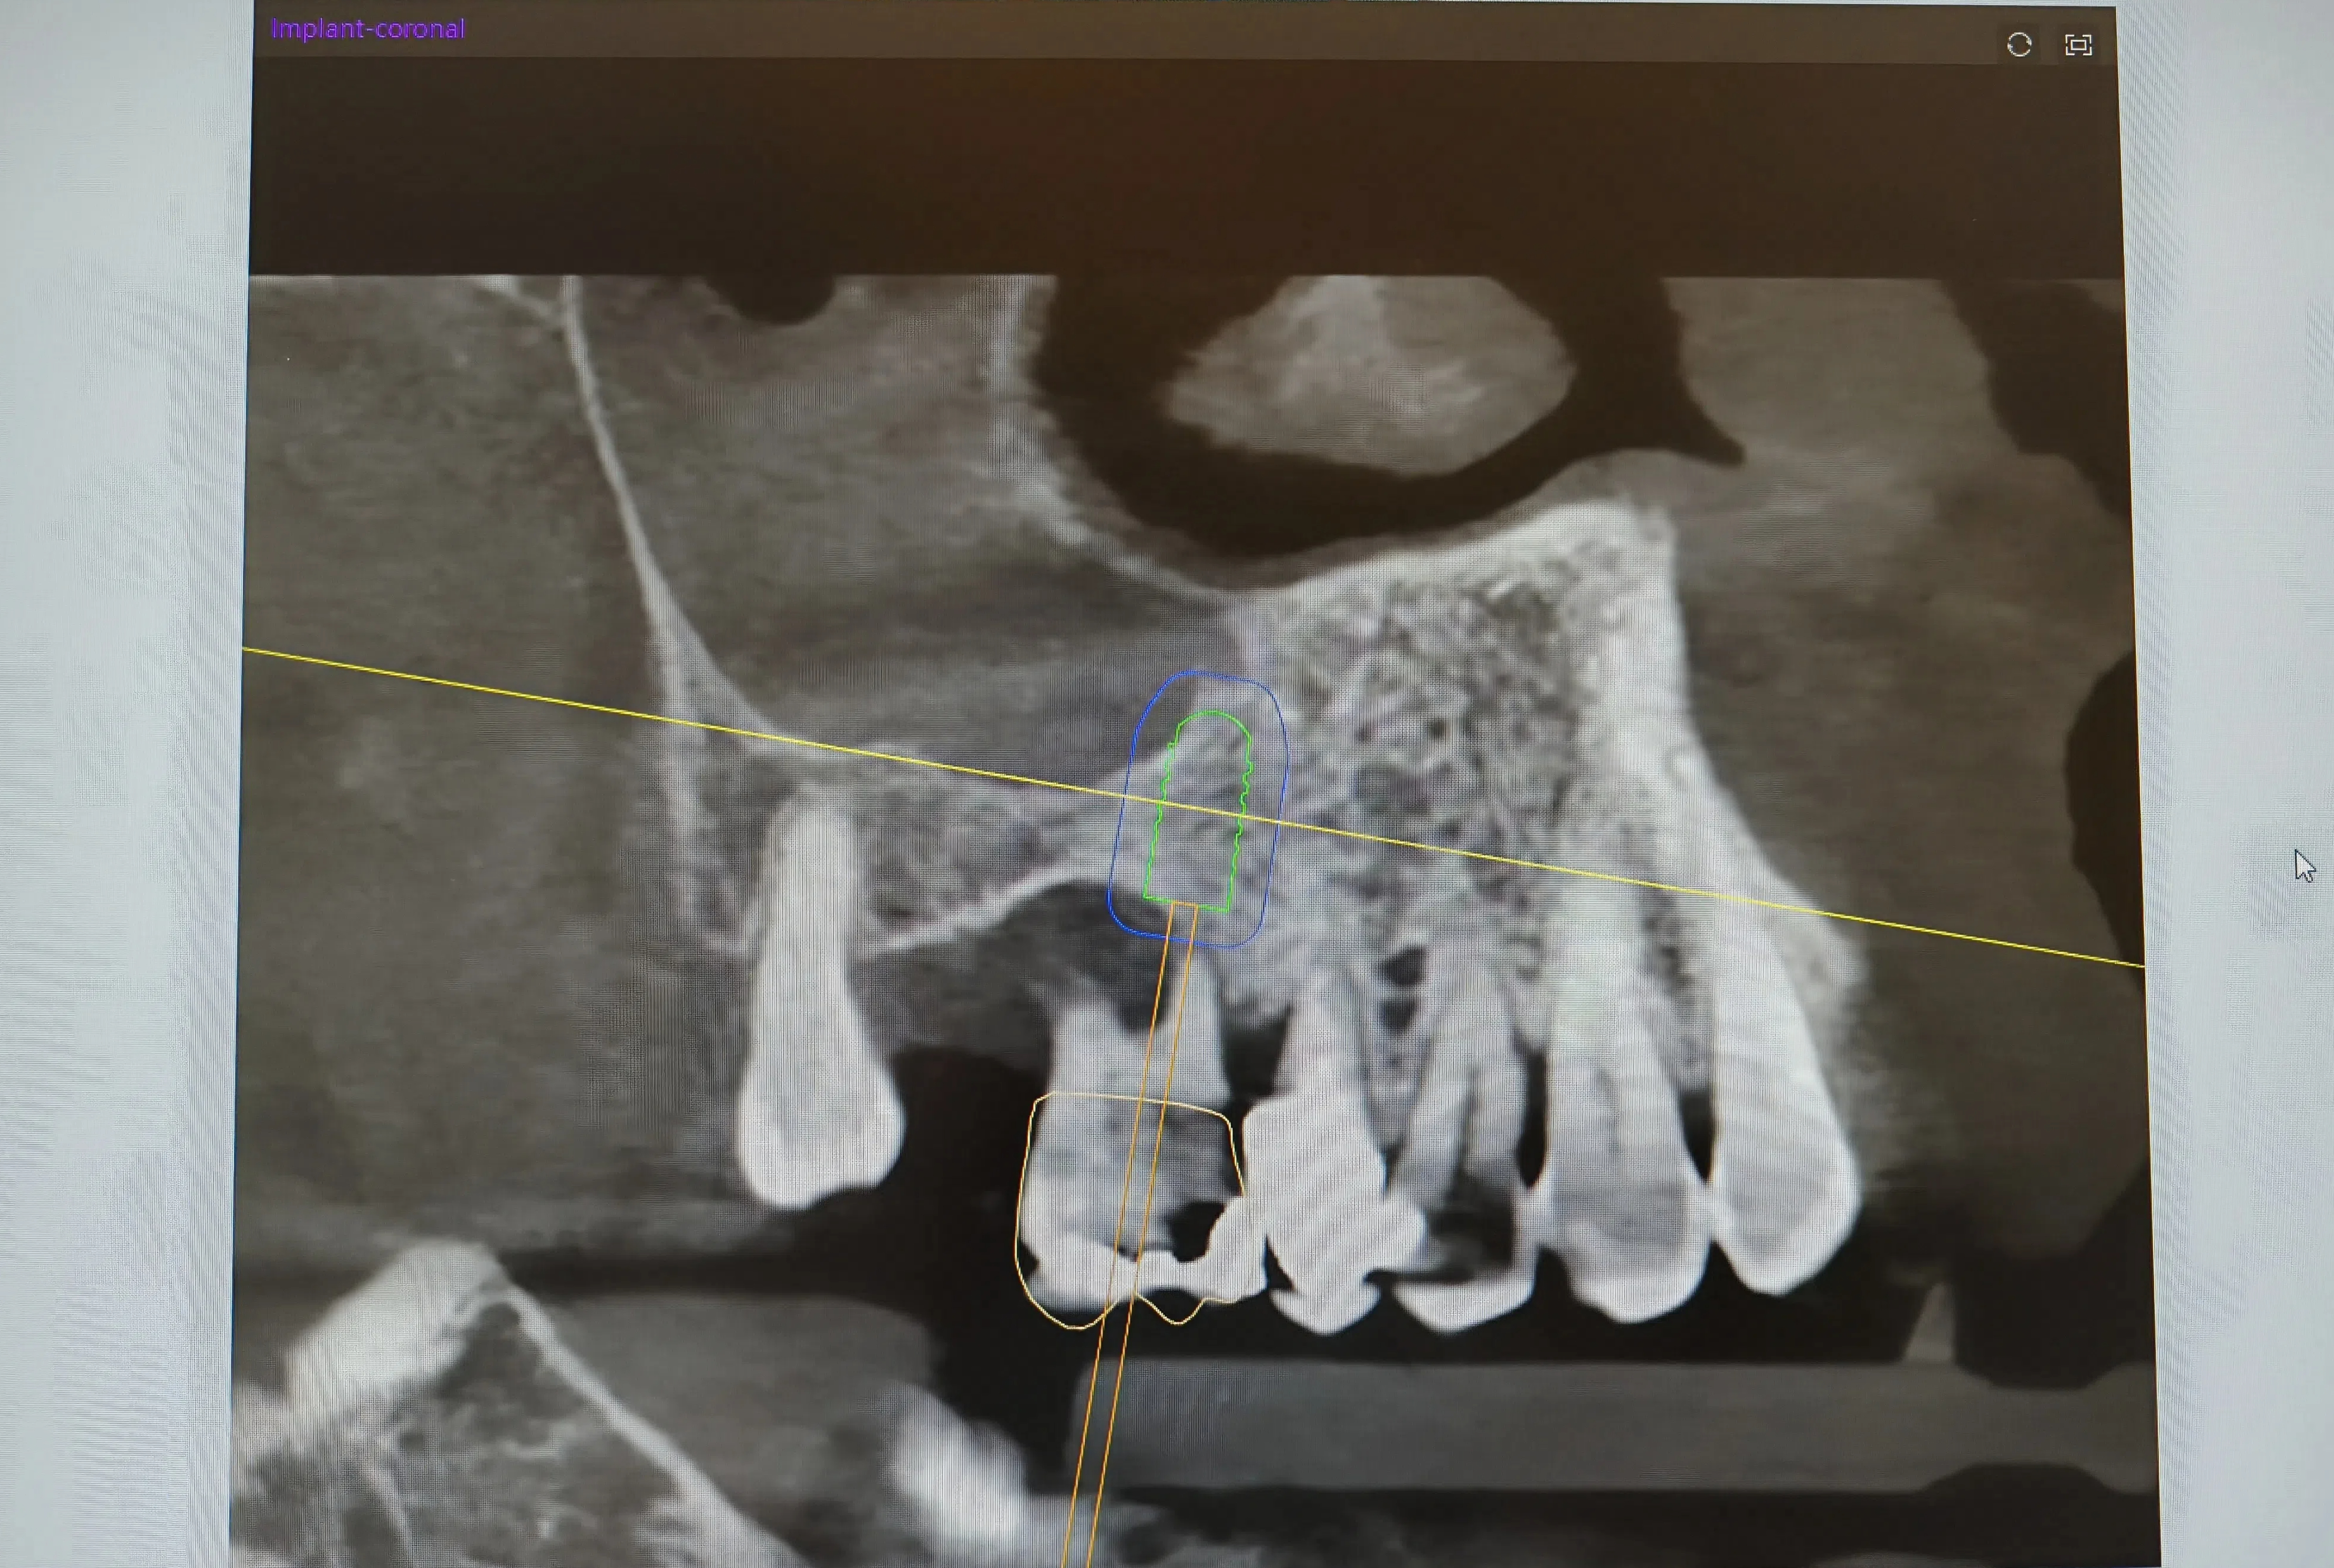

In Bologna, Italy, which is known as the "capital of oral implant art", Prof. Dr. Degidi's team was faced with a challenging case: the patient's maxilla was severely resorbed, with insufficient bone for traditional implantation; the distance from the neighboring curved root was 1.5mm, and the control of the micropointing angle required a high degree of control.

"It's like putting a GPS navigation on a tooth", Dr. Degidi compared in the interview after the successful completion of the operation, ”The Chinese technology allows us to see the ideal form of precise implantation."